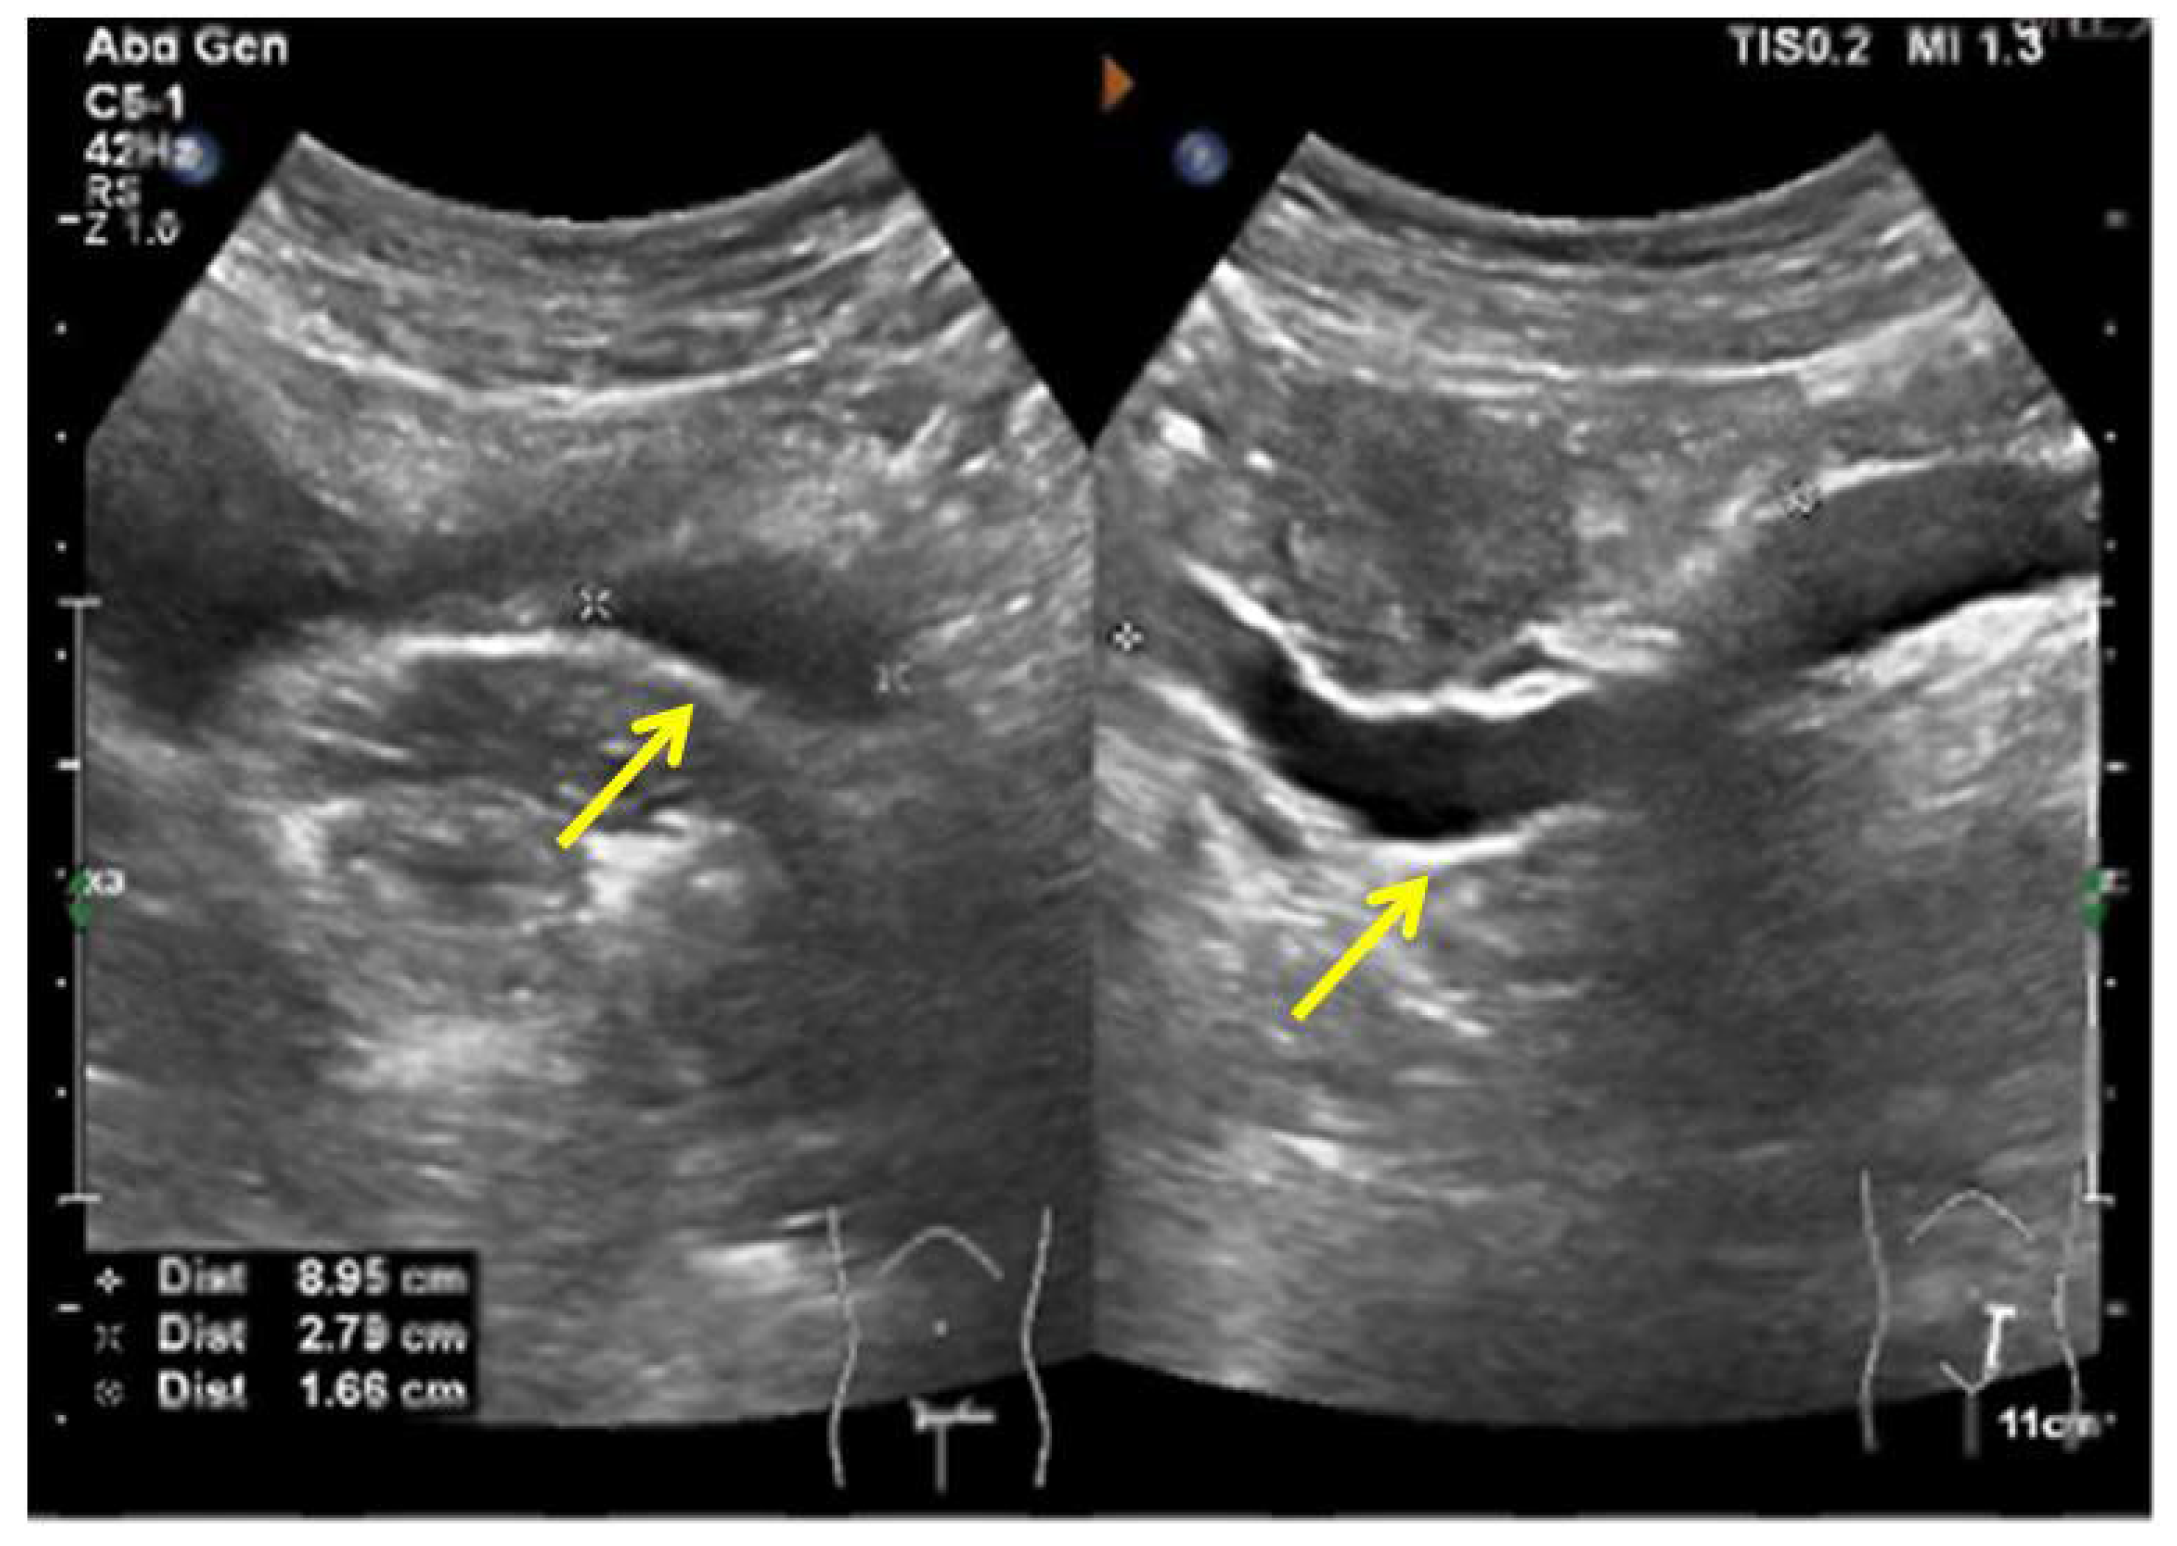

A 37-year-old woman was referred to our hospital for persistent vaginal discharge. After she underwent vaginal cyst excision 11 years ago, she began to experience persistent vaginal discharge, requiring two sanitary pads daily. A pelvic examination revealed a pinpoint-like hole in the right anterior wall of the vaginal fornix. It was observed that clear fluid was leaking from the hole, and a 3-centimetre in diameter cystic mass was palpated nearby. An MRU demonstrated that the duplicated renal pelvis was located at the upper pole of the right kidney. The left kidney and ureter were normal (Figure 8A). An MRU also revealed the dilated upper segment, thinned middle segment, and slightly expanded lower segment of the right duplicated ureter. Additionally, the distal segment of the duplicated ureter was enlarged to 1.7 × 1.3 cm, terminating at the right wall of the vagina. (Figure 8B). Consequently, the right ectopic ureter was separated at its base and reimplanted into the bladder.

Figure 8.

MRU demonstrated a duplex collecting system. (A) The duplicated renal pelvis (yellow arrow) was located at the upper pole of the right kidney. (B) The duplicated ureter (yellow arrow) drained into the right wall of the vagina.